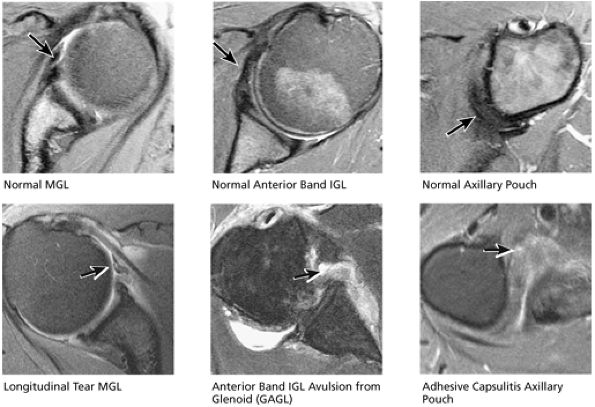

The MGHL is identified as a low-signal-intensity thin band or cord anterior to the anterior labrum, and the anterior band of the IGHL is between the anterior labrum and the subscapularis tendon. The MGHL may be closely applied to the anterior aspect of the anterior labrum or plastered against the subscapularis tendon, indistinguishable from the low-signal-intensity subscapularis without the benefit of intra-articular contrast. The SGHL is identified at the level of the coracoid and the biceps tendon.

-

With the arm abducted by the patient—s side, axial images through the inferior glenohumeral joint display the IGHL as a lax structure. The axillary pouch of the IGHL is identified inferior to the level of the bony glenoid and requires axial sections that extend inferior to the glenohumeral joint. The subacromial-subdeltoid bursa and the deltoid muscle can be identified between the rotator cuff and the acromion.

The low-signal-intensity glenoid labrum is also defined on sagittal images that transect the glenohumeral joint. The anterior band of the IGHL can be seen extending anterior and superior to become the anterior labrum. The MGHL is seen anterior to the anterior labrum. The subscapularis tendon is located anterior to the MGHL. This relationship is constant, even though the MGHL may be variable in size and shape. The MGHL may also be absent. The axillary pouch extends between the anterior and posterior bands of the IGHL.